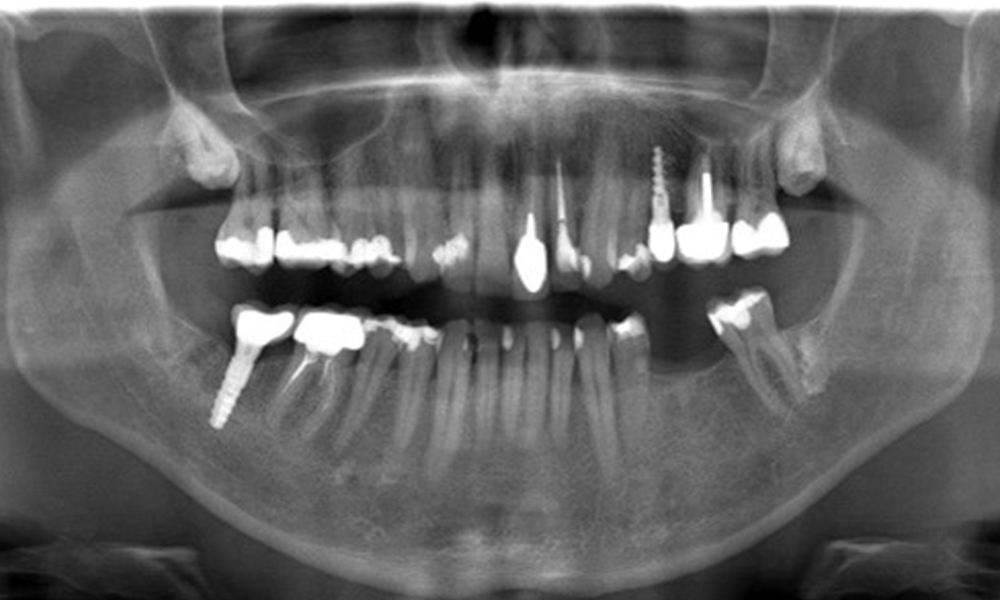

In the medical history, the 55-year-old patient states that he has no systemic disease and is not taking any medication. The patient’s lifestyle is similarly unremarkable. The patient has a few tooth restorations and two implants (2nd and 4th quadrants). On the basis of current findings, gingivitis is identified in an otherwise stable periodontal condition on the reduced periodontium (stage III, grade A).

Previous treatments: dental restorations (non-precious metal/ceramic blend), two implants (2nd, 4th quadrants)

The X-ray images show the bone loss.

OPG: 29/02/2024